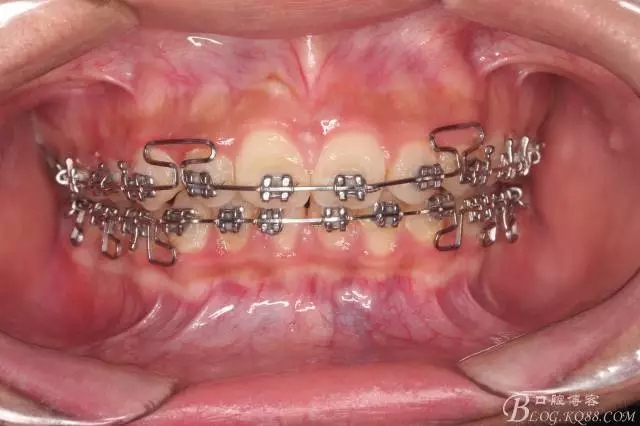

看看口內(nèi)照吧!真象“大暴牙”v假象“大暴牙”

三度深覆合,三度深覆蓋,尖牙,磨牙均二類關(guān)系!

佩戴三個(gè)月的FR2, 效果奇佳!前牙基本達(dá)到淺覆蓋,淺覆合!接下來進(jìn)入二期直絲弓固定正畸,排齊階段!

尖牙關(guān)系中性,磨牙關(guān)系中性,咬合鎖結(jié)良好!